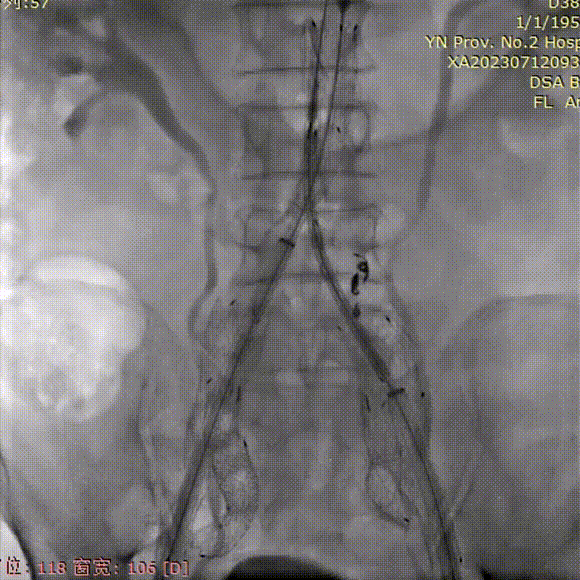

支架植入前造影

双侧股动脉入路,左侧置入18Fr 33cm GORE® DrySeal 亲水涂层导引鞘(以下简称“DSF导引鞘”),右侧置入12Fr 45cm DSF导引鞘;建立翻山通路后将标记猪尾导管头端置于肾动脉开口上方,做腹主动脉造影:显影显示双侧髂总动脉瘤;肾动脉开口到右髂内距离约200mm。